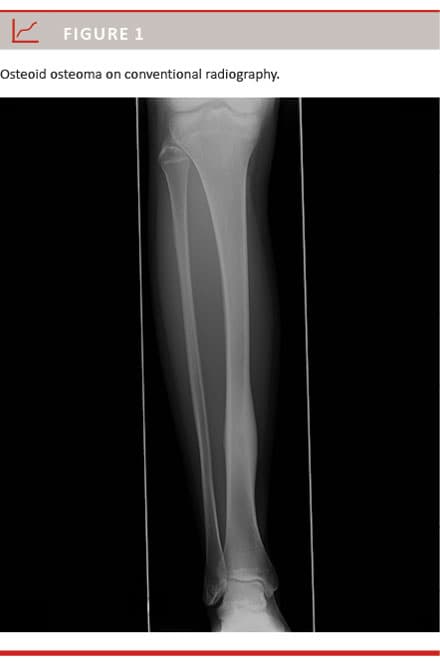

The radiological diagnosis is based on conventional radiography, the characteristic feature of which is an oval radiolucency area representing the nidus sur-

rounded by reactive bone sclerosis (Figure 1). The diagnosis may also be established by computed tomography (CT) where the characteristic appearance of OO is a low-attenuation nidus with a varying amount of bone sclerosis (Figure 2). Occasionally magnetic resonance imaging (MRI) and rarely bone scintigraphy are preformed to confirm the diagnosis [4, 6]. Bone scintigraphy is made with Tc-99-labelled diphosphonates, which accumulate in areas with increased osteoblastic activity and bone turnover and therefore have a markedly increased uptake in the nidus [4].